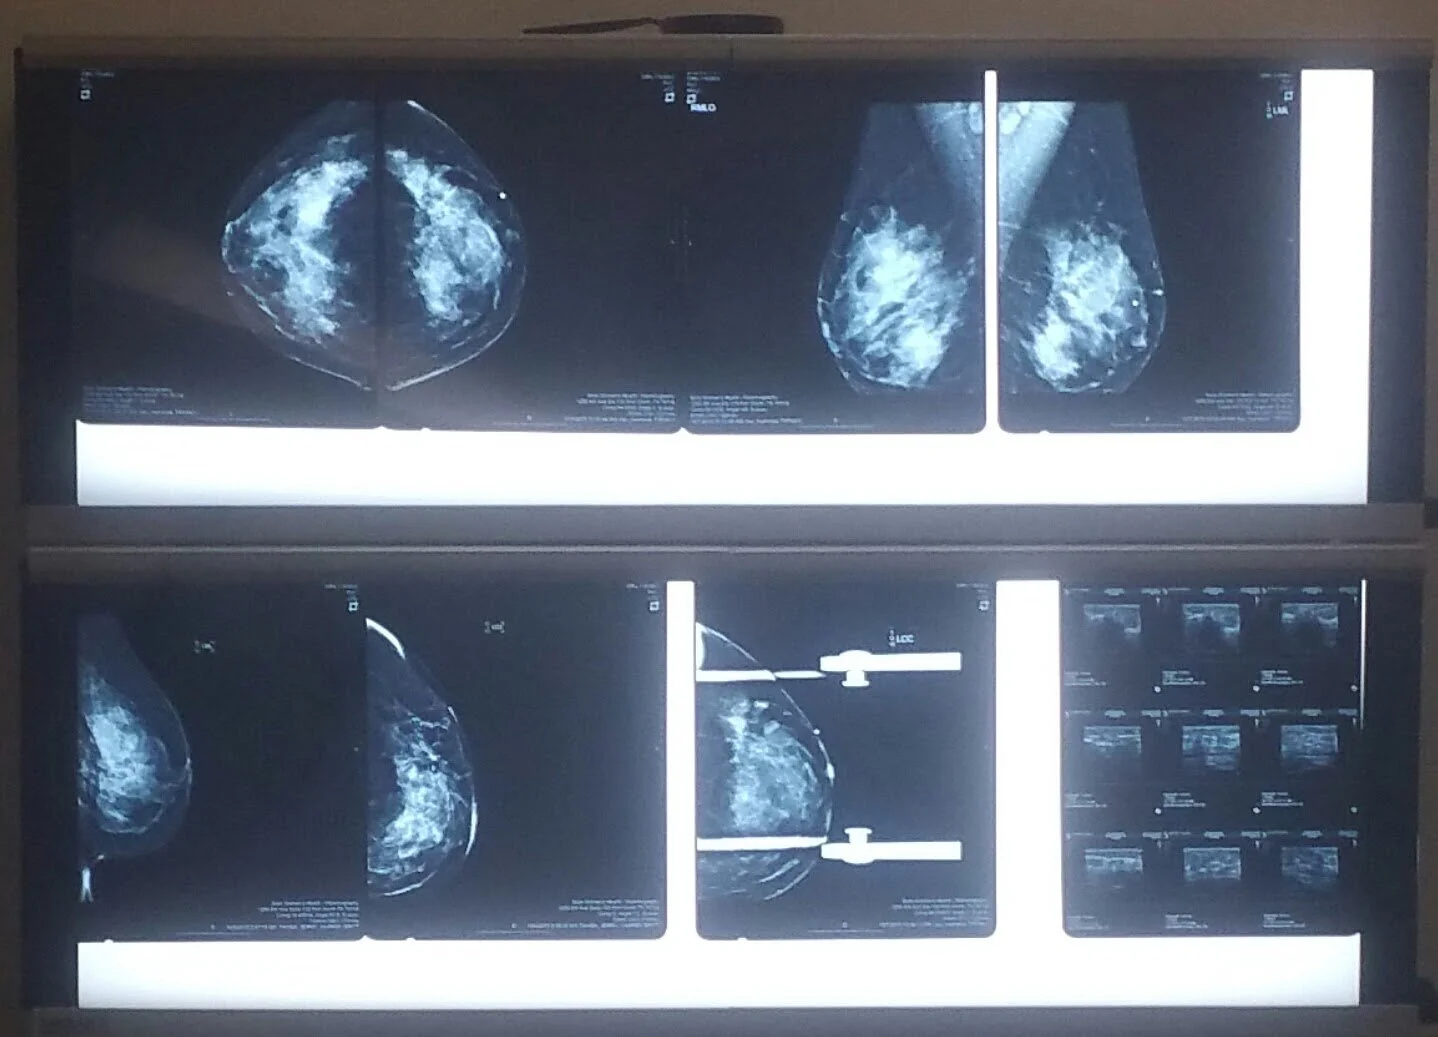

I started this Non Profit a year after beating breast cancer the first time. I was first diagnosed with breast cancer in October 2015. I actually found the cancer myself. When I was diagnosed I was stage III b. I had my first surgery December 11 of 2015. I started chemo January 15. I had to go through four rounds of chemo. I finish chemo treatment on March 19. I then had to go through 49 rounds of radiation. A year and a half later after beating breast cancer the first time, it came back on the right side. They went in and cut out all my breast tissue on my right side and then proceeded to do reconstruction surgery. October 26 of 2019 I will celebrate being in remission two years. I started this nonprofit after beating breast cancer because I was so thankful to be alive. I became a single mother at 16. I can remember not being able to get the things I needed for my children. I also remember how hard it was around Christmas time. We want to give these families hope !!! We want to show them kindness, and empathy !! I love helping people, edit has actually become addicting !! If we had more people in our world giving back to our community and showing kindness and empathy and love to our community the world would be such a better place.

My tumor was 5 cm

I also had to have 15 lymph nodes removed.

out of that 15 there were 13 positive for cancer. My cancer was estrogen fed and was eating off my estrogen in my body.